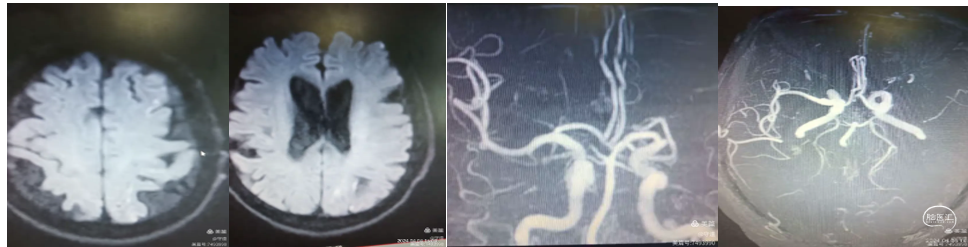

患者男性,83岁,既往房颤病史多年,以"右侧上下肢无力,言语含糊,烦燥2小时"入院。核磁显示:左侧大脑半球多发点状梗塞,老年性脑萎缩。MRA显示:左侧大脑中动脉M1起始部闭塞,未向远端供血。

造影显示血管血流通畅达3A级,远端血管血流显影良好,未见明确逃逸征象。M1段残余狭窄约40~50%,不影响血流供应,未一期置入支架,服药观察。

术后1月再次以言语不利,右侧上下肢力弱再次住院。MRA显示左侧大脑中动脉M1段重度狭窄,急性闭塞并发梗塞风险高。